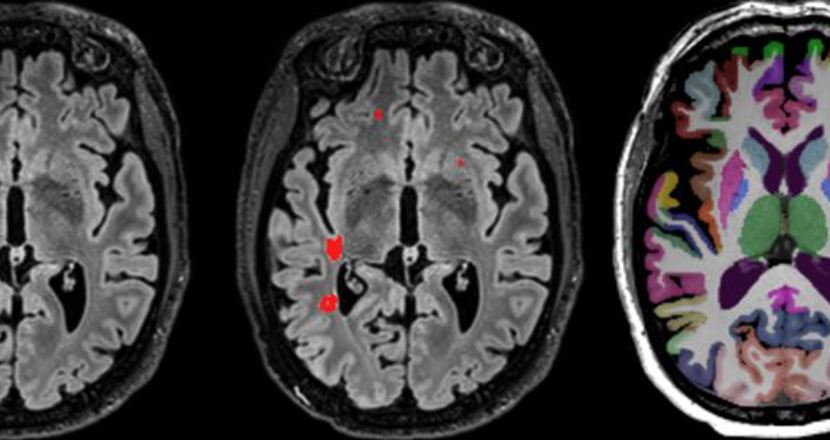

Bilder tagna på hjärnan med MR-kamera

Foto: Karolinska Universitetssjukhuset

Karolinska Universitetssjukhuset har invigt en ny magnetkamera i Huddinge. Det är det första sjukhuset i världen som har en ny generations magnetkamera i klinisk drift. Magnetkameran har ett magnetfält på 7 Tesla, det starkaste som någonsin använts inom rutinsjukvård.

– Med den nya magnetkameran kan vi göra mer noggranna MR-undersökningar för patienter än vad som tidigare varit möjligt. Tack vare bättre bildkvalitet för hjärnan kan vi ge rätt diagnos i ett tidigare skede och optimera behandlingen, säger specialistläkaren Tobias Granberg som är sektionschef inom neuroradiologi på Karolinska Universitetssjukhuset.

Magnetkameran kommer att vara särskilt betydelsefull vid bland annat epilepsi, MS, ALS, Parkinsons och Alzheimers sjukdom.

– Till exempel kan vi hos var tredje person med epilepsi som inte svarar på läkemedelsbehandling nu hitta förändringar som kan opereras som vi inte ser med vanlig magnetkamera. Vid MS kan vi nu se hur sjukdomen påverkar hjärnbarken och påvisa kronisk inflammation. Det gör att vi kan hitta nya läkemedel som förhindrar kroniska funktionsnedsättningar, säger Tobias Granberg.